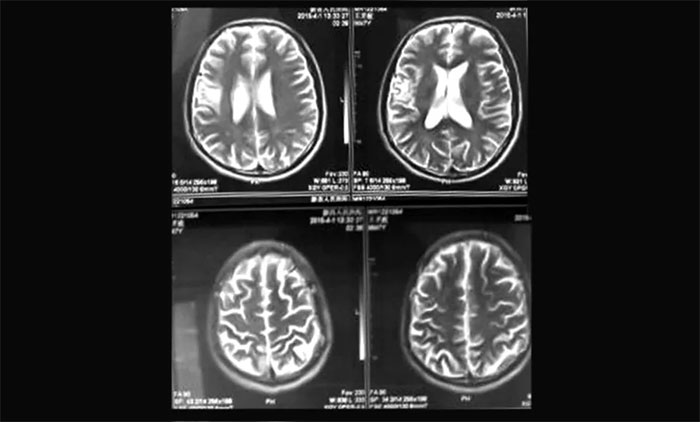

▲ 复查病灶畸形血管巢已基本消失

通过完善相关检查并征得患者家属同意后,陈琦主任团队为胡某开展了头部伽玛刀治疗,过程顺利。后期通过复查评估,患者畸形血管巢已基本闭塞,未出血,头痛等临床症状得到明显缓解。